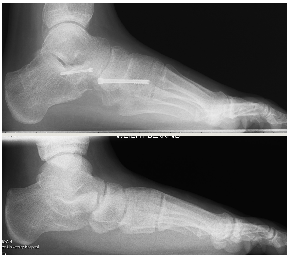

Hoke (Navicular cuneiform fusion)

The pathological flat foot tends to sag at the navicular cuneiform joints. Given time the loss of alignment is fixed, often with arthritis present. Taking a wedge to correct the arch and reduce the instability is a common adjunctive procedure providing good stability to the arch.

These X-rays show the foot from the side with initially a loss of arch height and a midfoot sag, in a young adult. Post procedure the lateral column has been lengthened using an Evans procedure with a navicular cuneiform fusion.

This has now been successfully realigned.